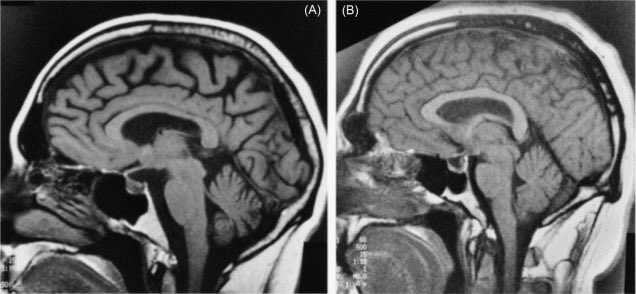

7️⃣تشخيص ضمور المخ

عادةً مايتضمن التشخيص اختباراً بدنياً يتبعه اختباراتٍ معينةٍ،ويظهر ضمور الدماغ في عمليات مسح تصوير الدماغ منها:

*الرنين المغناطيسي(MRI)الذي يخلق صوراً دماغيةً عالية الدقة للتشخيص